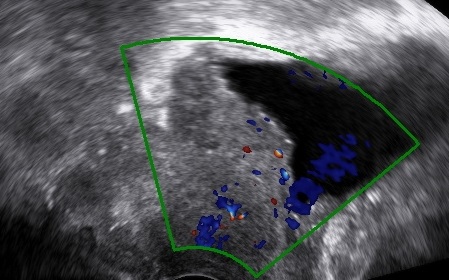

HomeGynecology Gynecology Vaginal Inclusion Cyst Laparotomy for Giant Ovarian Tumor Fallopian Tube Torsion Vesicovaginal fistula after hysterectomy Parasitic Myoma Smooth Muscle Tumor of Uncertain Malignant Potential (STUMP) Mucinous Cystadenoma Hysteroscopic Myomectomy Laparoscopic Excision of a Mesothelial Cyst of the Uterus Laparoscopic Treatment of A Chronic Ectopic Pregnancy Laparoscopic Removal of an intraabdominal IUD Paraovarian / Paratubal Cyst LAparoscopic Supracervical Hysterectomy (LASH) Laparoscopic Myomectomy Laparoscopic Management of Tubal Ectopic Pregnancy #2 Salpingectomy Laparoscopic Management of Tubal Ectopic Pregnancy #1 Salpingotomy Masterclass – Ultrasound Study of the Tubal Ectopic Pregnancy Total Laparoscopic Hysterectomy (TLH) Laparoscopic Management of an Immature Teratoma Ultrasound Study of Borderline Ovarian Tumors Laparoscopic Bilateral Salpingectomy: Tips & Tricks Transcervical Resection of the Endometrium Ultrasound Study of Cervical Cancer Pelvic Lymphoma Ureterovaginal fistula after hysterectomy Adenomyosis How to optimize your ultrasound image Hematometra after conization Endometrial Cancer Hemoperitoneum Endometrioma Infectious non-puerperal mastitis Hydrosalpinx Adnexal torsion Deep infiltrating endometriosis Struma ovarii Caesarean scar pregnancy Interstitial pregnancy Cervical pregnancy Share this: Share on X (Opens in new window) X Share on Facebook (Opens in new window) Facebook Share on LinkedIn (Opens in new window) LinkedIn